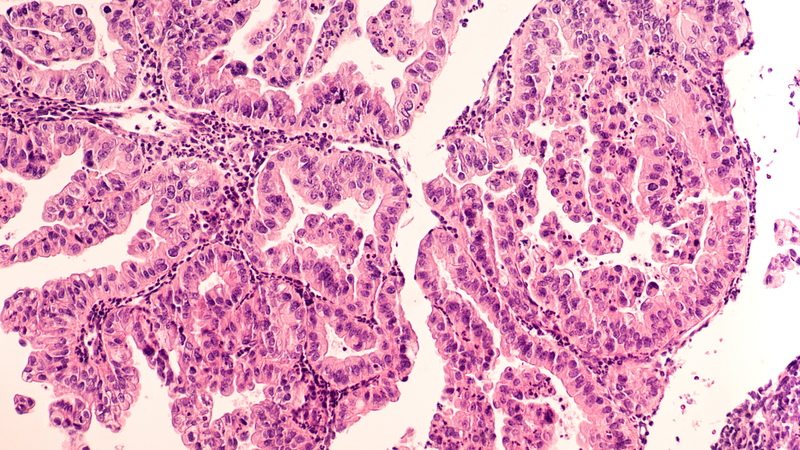

The study published in the journal 'Nature Communications' showed the superior therapeutic effectiveness of the 'one-two punch' on cells of ovarian cancer patients, based on the manipulation of the state of cellular aging. "In the case of epithelial ovarian cancer (EOC)--the most common and lethal ovarian cancer--we act in two stages. First, we force the cancer cells to age prematurely i.e., we force them into senescence. This is the first therapeutic punch. We throw our second punch using senolysis, destroying and eliminating them. This strategy requires excellent coordination of the two steps," explained Francis Rodier, a researcher at the Universite de Montreal.

The team of researchers, led by Rodier and his colleague Anne-Marie Mes-Masson, discovered that EOC cells enter senescence following chemotherapy in combination with PARP inhibitors. PARPs are enzymes that help repair damage to DNA. By blocking PARPs, PARP inhibitors prevent cancer cells from repairing their DNA, stop them from proliferating and cause them to age prematurely.